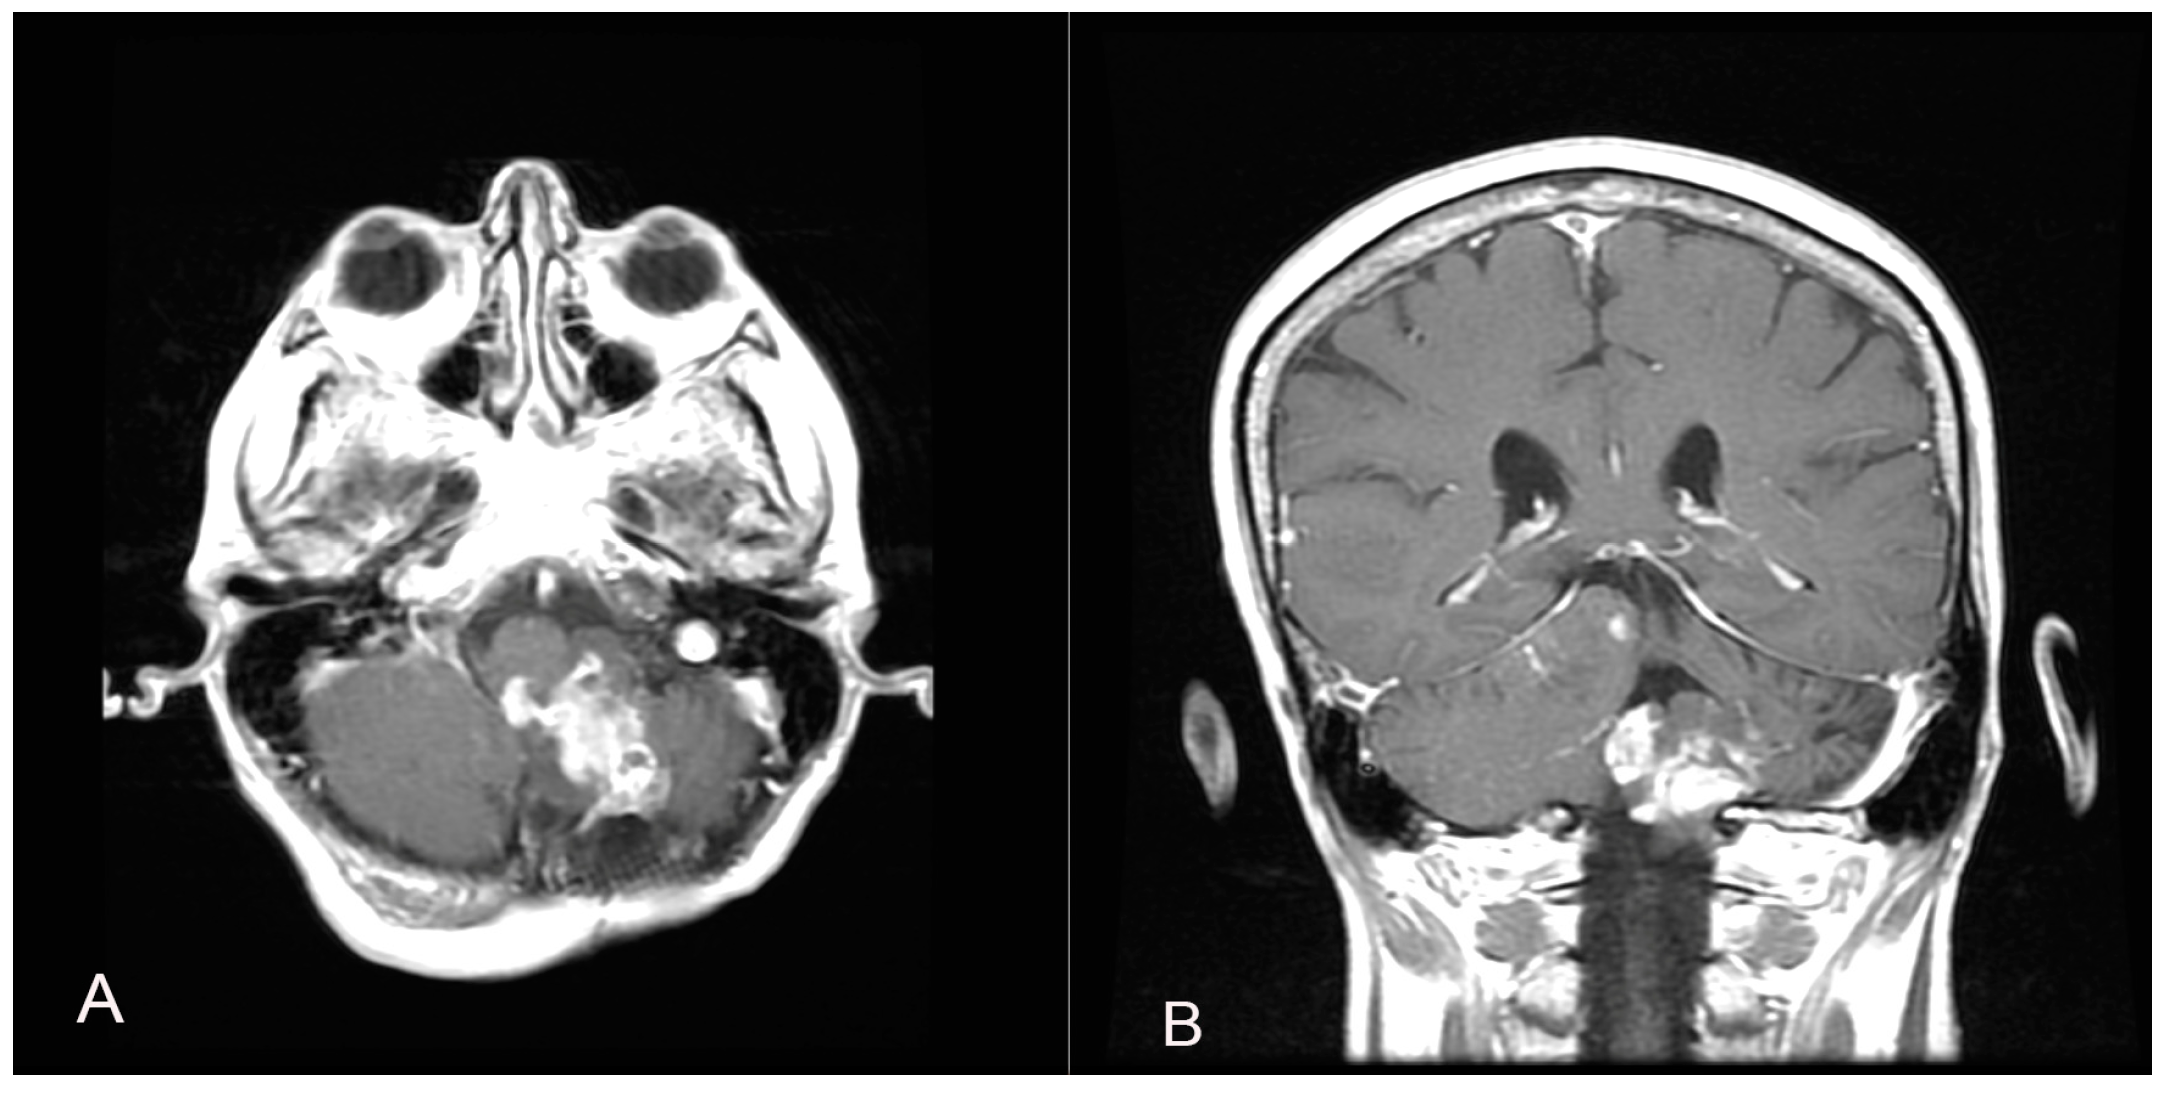

Two years later, a recurrence in the left cerebellar area with inhomogeneous enhancement of 4.5 mm × 15 mm was documented (Figure 4). The patient developed gait disturbances, bilateral left heartbeat nystagmus, a positive Romberg sign, finger-to-nose dysmetria on the left and heel-to-knee dysmetria on the right. A second surgery was performed through a telo-velar approach. The lesion appeared to be a calcified mass tenaciously attached to contiguous structures. A portion of the tumor was found to be tightly adherent to the left lateral recess, which was left in situ after a positive irritative response during the neurostimulation of the XII cranial nerve. The procedure was entirely supported by intraoperative neurophysiological monitoring. The subsequent postoperative course was uneventful (Figure 5). Histopathological examination was consistent with the previous findings of low-grade glioneuronal neoplasia. This entity, not specifically categorized in the current classification (WHO 2021), could be referred to as an infratentorial glioneuronal tumor (Figure 6).

Figure 4.

A follow-up contrast-enhanced brain MRI two years after the first surgical intervention shows the presence of a recurrence in the left cerebellar area with inhomogeneous enhancement (A,B).